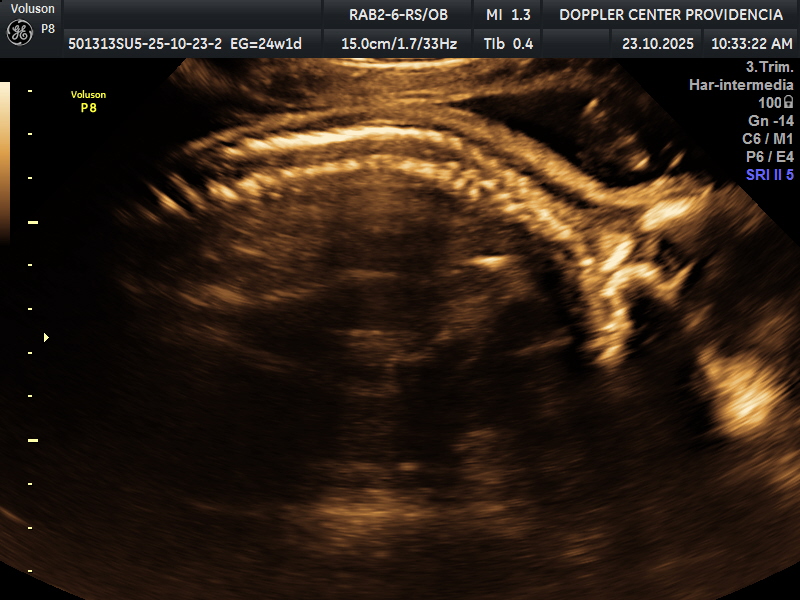

• Eco Doppler 22-24 semanas